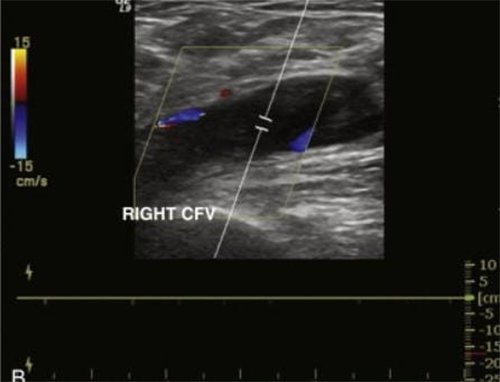

Outcomes observed in patients treated with image-guided, minimally invasive vascular procedures.

Results vary by patient and condition. Images are for educational purposes only.